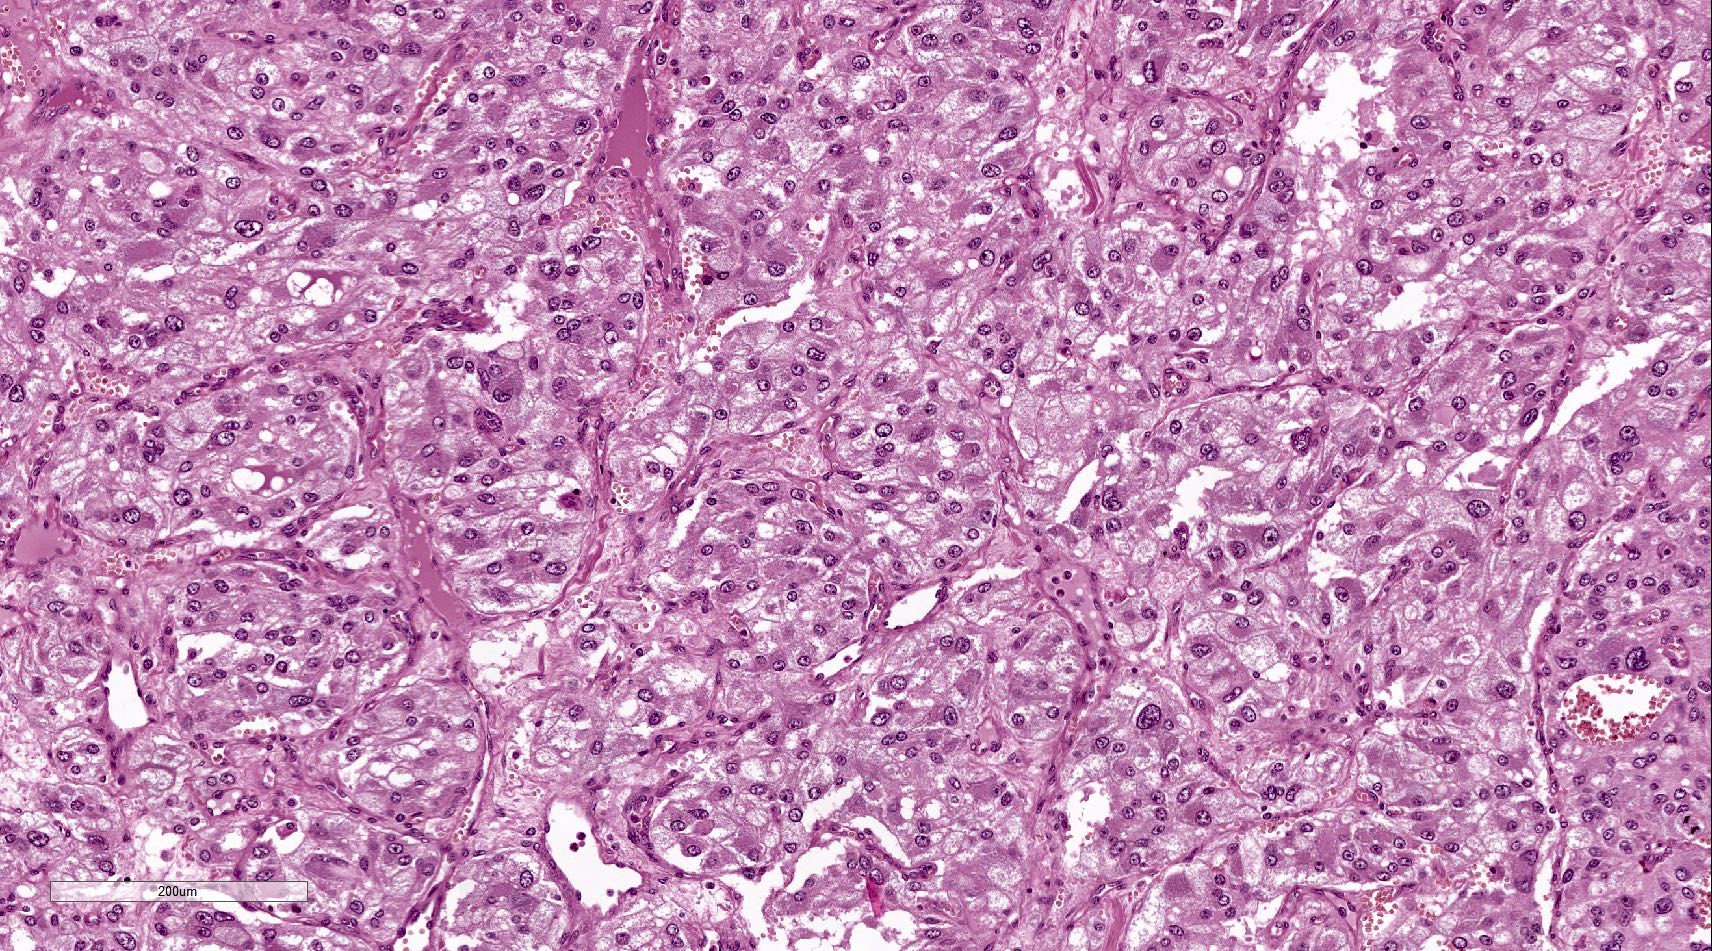

Microscopic (histologic) description

- Prevailing histologic pattern: epithelioid chief cells arranged in distinctive clusters / nests (zellballen pattern), separated by prominent fibrovascular stroma (J Clin Med 2018;7:280)

- Trabecular pattern: ribbons or cords of epithelioid cells divided by fibrous bands

- Other patterns: pseudorosette, angioma-like, spindled and sclerosing

- Chief cells: round, oval to polygonal cells with abundant granular basophilic, eosinophilic or amphophilic cytoplasm (Surg Pathol Clin 2019;12:951)

- Intracytoplasmic hyaline globules may be present in sympathoadrenal paragangliomas

- Giant multinucleated cells and bizarre cells can be present (Srp Arh Celok Lek 2002;130:7)

- Rarely, elongated and spindle shaped cells with a sarcomatoid appearance may be found

- Scattered ganglion cells can be seen

- May have nuclear atypia

- May have dysmorphic vessels, melanin-like pigment (neuromelanin) (pigmented paraganglioma), amyloid, abundant stroma and osseous metaplasia (Diagn Pathol 2012;7:77, Hum Pathol 1992;23:33)

- No or rare mitotic figures except in highly aggressive rapidly proliferating lesions

- May have focal chronic inflammatory infiltrate

- Necrosis is unusual except in patients who have undergone preoperative tumor embolization

Microscopic (histologic) images

Contributed by Luvy Delfin, M.D. and Sylvia L. Asa, M.D., Ph.D.